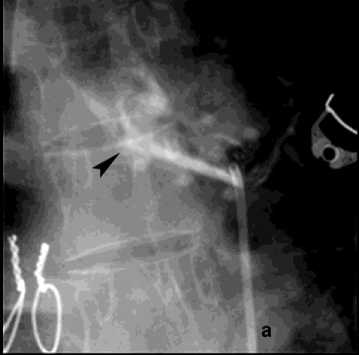

Рисунок 9. Аортография у пациента после трансплантации лёгких, ЛК 3Б: а – аорто-бронхиальный свищ с поступлением контраста в левый главный бронх; б – эндопротезирование нисходящего отдела аорты протезом Ankura TAA2622B160 – без признаков экстравазации

Figure 9. Aortography in a patient after lung transplantation, PH grade 3B: a – aortobronchial fistula with contrast extravasation into the left main bronchus; б – endovascular repair of the descending aorta with Ankura TAA2622B160 stent graft – no signs of extravasation

В общей сложности погибло два пациента с аорто-бронхиальными свищами и ЛК3Б. Причиной кровотечения в одном случае у пациентки 86 лет явилось расслоение грудного отдела аорты с прорывом в бронх, в другом – у пациентки 31 года после трансплантации лёгких, стентирования стриктуры левого долевого бронха вызвало в последующим пролежень аорты. После эпизода массивного ЛК пациентам проведён полный комплекс гемостаза, включая стентирование аорты (1), санацию трахеобронхиального дерева (2), бронхоблокацию, на фоне ИВЛ (2) (рис. 9, б).